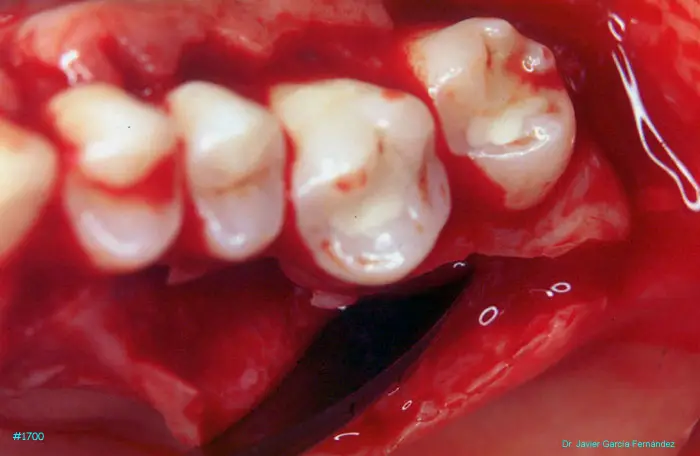

Atlas of Surgical Techniques in Periodontics. Chapter IV. Atlas de Técnicas Quirúrgica en Periodoncia

image 211